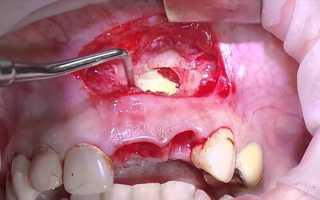

Если киста в челюсти продолжает расти после проведенных процедур, врач может применить апикальный хирургический метод лечения. Во время этой процедуры хирург очищает содержимое кисты и удаляет инфицированный корневой кончик зуба. Затем проводится пломбирование изнутри и разрез сшивается. Если киста в нижней или верхней челюсти образуется повторно, то может потребоваться удаление зуба и установка имплантата. Современные стоматологические методы позволяют решить эту проблему, сохраняя при этом зуб.